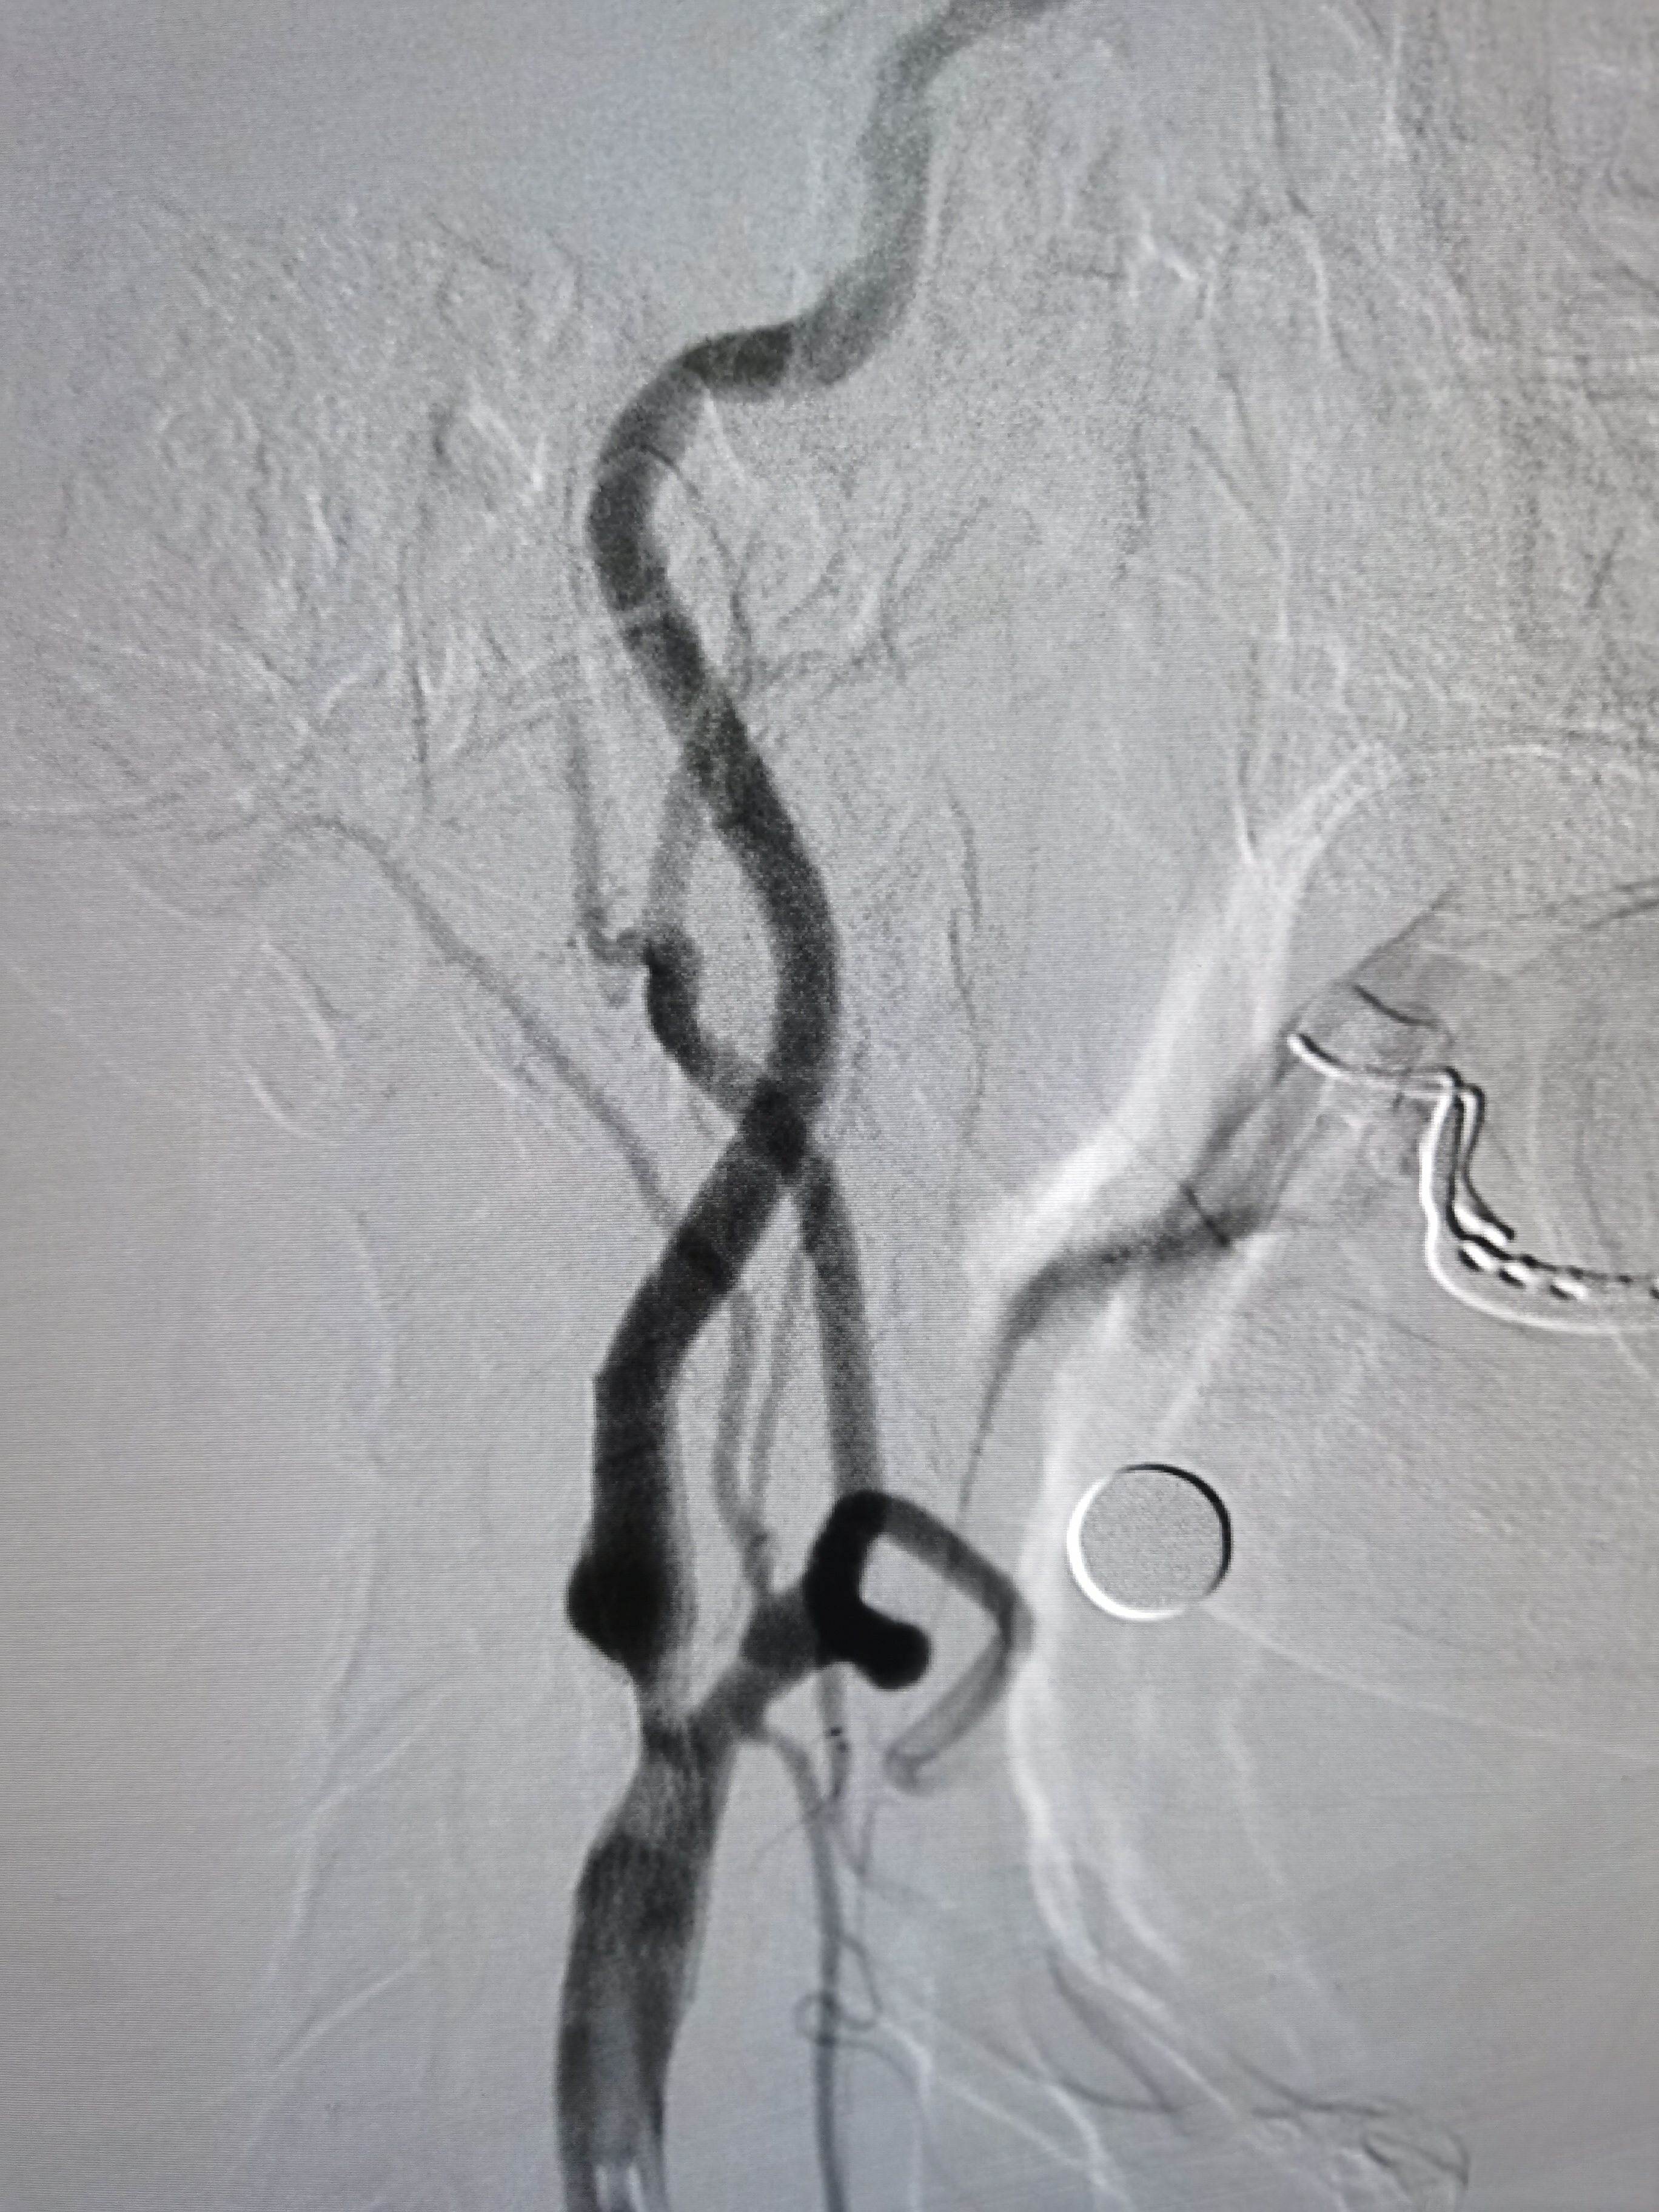

撤出保护伞,造影见狭窄改善明显。

术前术后对比

术毕,撤出各级导管,缝合股动脉。术后给予积极控制血压,避免高灌注损伤,患者病情平稳,无不适主诉。